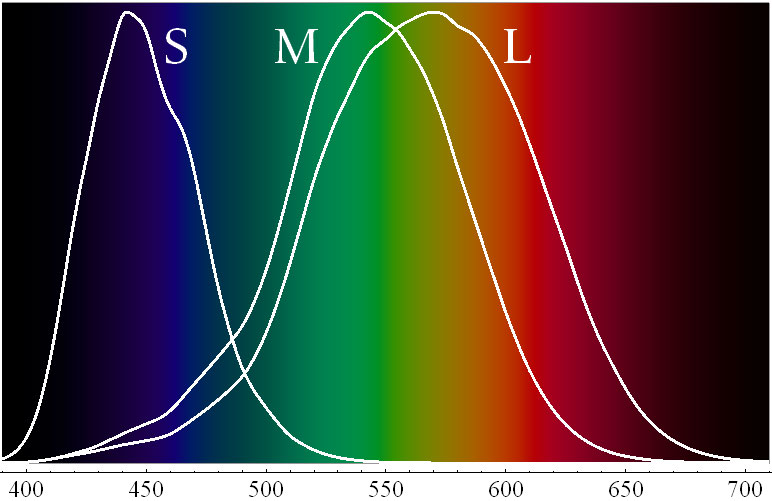

چرا در کمترین زمان

سلولهای مخروطی نوعی از سلولهای گیرندهٔ نورهستند که در شبکیه چشم قرار دارند و در دید رنگی نقش دارند اگر شما بیش از 30-20 ثانیه به یک نقطه تمرکز کنید دیگرقادر به تشخیص بهتر رنگ ها نخواهید بود زیرا چشم ها انرژی لازم ATP)) برای تشخیص و تمییز طیف رنگ ها را از دست می دهند. این سلولها بر اساس تحریک پذیری خود نسبت به طول موجهای مختلف نور بر سه دسته تقسیم میشوند:

سلولهای مخروطی نوع S که موجب دیدن رنگ آبی می شود .

سلولهای مخروطی نوع M که موجب دیدن رنگ سبز می شود .

سلولهای مخروطی نوع L که موجب دیدن رنگ قرمز و زرد می شود .

که اختلال در هر از این سلول ها باعث کور رنگی افراد می شود.

منحنی نشاندهندهٔ میزان تحریک هر کدام از ۳ نوع سلول مخروطی با توجه به طول موج.